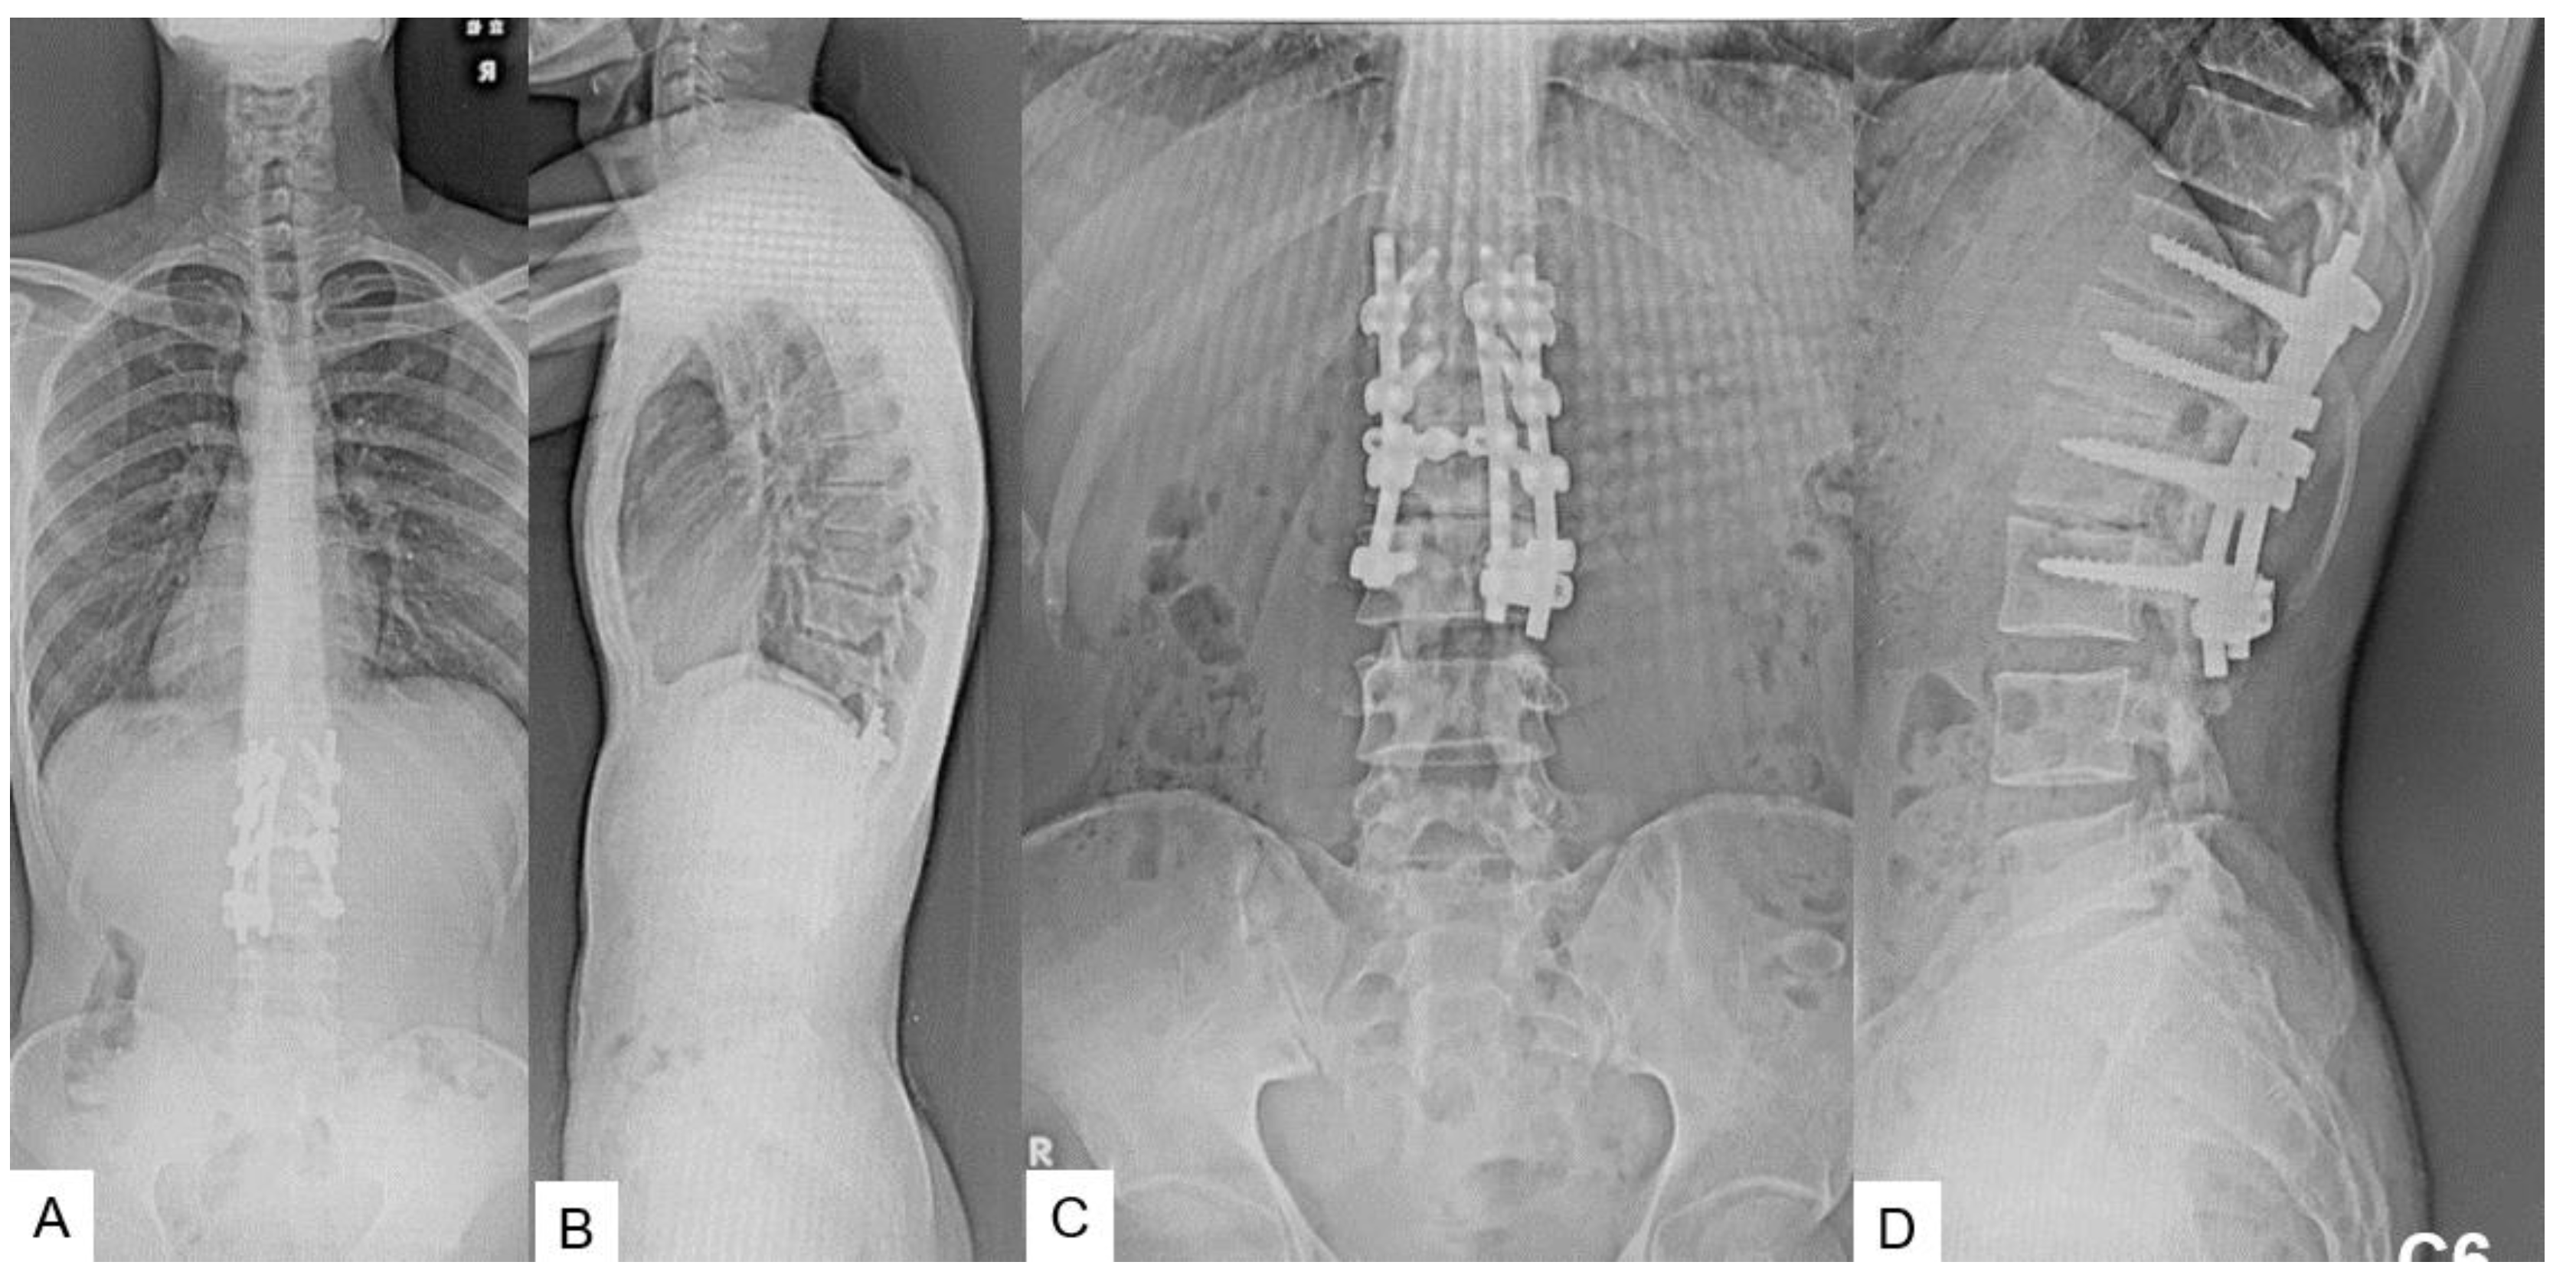

2.5. Postoperative imagings.

2.6. One year follow-up